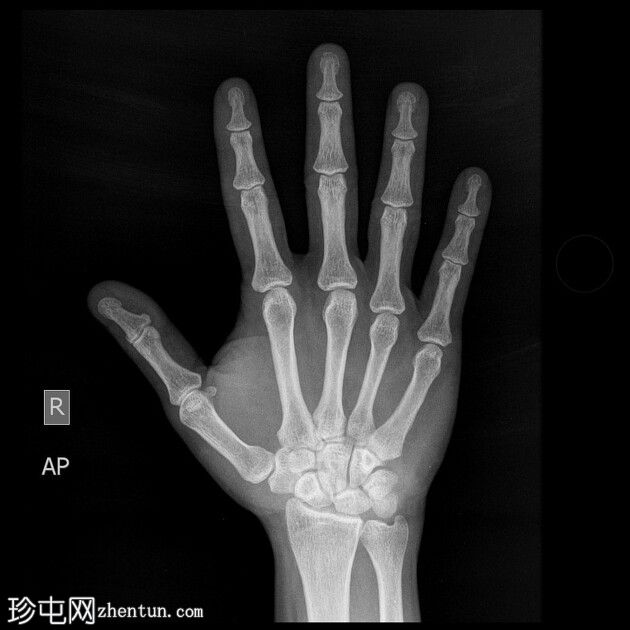

正面

右手X光片显示中指远端指骨末端失去正常的光滑轮廓,皮质轮廓不规则,提示远端骨折畸形。骨折在斜位片上更容易被看到,并伴有轻度移位和周围软组织肿胀。

X光片结果显示中指远端指骨末端骨折,皮质轮廓不规则,正常轮廓丧失,可能由直接创伤引起,例如重物撞击或挤压伤。